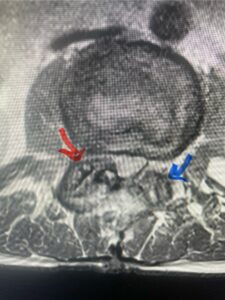

In this next case, this patient is a 47 year-old female who presents with intractable low back pain with severe pain, numbness, and weakness in the right lower extremity that had gotten progressively worse over a year. The patient had failed conservative management including physical therapy and epidurals. She was noted to have ⅘ weakness of plantar flexion. MRI demonstrated a large right L5-S1 disc herniation with severe compression of the descending right S1 nerve root (Fig 3). It was decided to perform a right L5-S1 hemilaminectomy for removal of the disc fragment and decompress the S1 nerve root. When you expose the disc, one must be certain to release any anterior adhesions to the nerve root in order to prevent a dural tear during retraction of the nerve root. It is also important to make sure during exposure and you finally encounter the dura after removing the ligamentum and fat, to make sure you are looking at the nerve root and not the main trunk of the thecal sac because if you don’t you can avulse or damage the nerve root if you retract the wrong structure.

Fig. 3a: Sagittal and axial T2-weighted lumbar MRI images demonstrating large right L5-S1 disc herniation (red arrows)